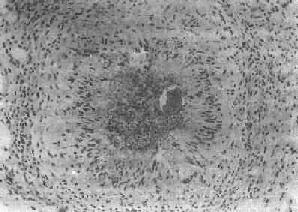

图19-6 血吸虫病之晚期急性虫卵结节 坏死区及嗜酸性粒细胞浸润范围缩小,其周围出现放射状排列的类上皮细胞层 (2)慢性虫卵结节:急性虫卵结节经10余天后,虫卵内毛蚴死亡,坏死物质逐渐被吸收,虫卵破裂或钙化,其周围除类上皮细胞外,出现异物巨细胞和淋巴细胞,形态上似结核结节,故称为假结核结节(图19-7)。少数虫卵结节一开始即为假结核结节,而不经过急性虫卵结节阶段。最后,假结核结节中的类上皮细胞为纤维母细胞代替,并产生胶原纤维,使结节纤维化。其中央的卵壳碎片及钙化的死卵可长期存留。

图19-7 血吸虫病之慢性虫卵结节 结节中央有破裂和钙化的虫卵,其周围有类上皮细胞和异物巨细胞,形成假结核结节 目前认为虫卵结节的形成主要是由T细胞介导的迟发性变态反应的结果。诱发虫卵结节的抗原来自成熟虫卵中毛蚴所分泌的可溶性卵抗原(soluble egg antigen,SEA),是一种含蛋白质、糖蛋白、多糖和酶的异质性混合物,其糖蛋白中的某些成分,如MSA,gp-2是引起虫卵肉芽肿的主要抗原。活毛蚴分泌的抗原,透过卵壳上的微孔,持续稳定地释出,使机体致敏。经巨噬细胞吞噬、加工的抗原,传递给辅助性T细胞(TH),致敏的TH产生多种淋巴因子,如巨噬细胞激活因子(MAF)、嗜酸性粒细胞趋化因子(ECF)等,引起巨噬细胞和嗜酸性粒细胞等聚集于虫卵周围而形成虫卵肉芽肿。实验证明淋巴细胞或抗巨噬细胞的血清、细胞免疫抑制药物等均能抑制致敏小鼠虫卵肉芽肿的形成。新生期摘除胸腺的小鼠和先天性无胸腺裸鼠体内形成的虫卵肉芽肿均较对照组小。致敏小鼠和感染小鼠的淋巴细胞可将致敏被动地转移给受体小鼠,这些都说明T细胞在虫卵肉芽形成过程中起重要作用。除细胞免疫外,在急性虫卵结节形成过程中,毛蚴分泌的SEA刺激宿主产生抗体,在虫卵周围形成免疫复合物,Ⅲ型变态反应亦可能参与虫卵结节的形成。 这种肉芽肿的形成是宿主对虫卵的一种免疫应答,使虫卵变性、破坏、被吞噬和清除,还可以隔离和中和虫卵释放的抗原及毒性物质,起局部免疫屏障作用。另一方面,在早期肉芽肿内即可测出纤维连结蛋白(FN),体外培养的肉芽肿能分泌纤维母细胞生长因子(FGF),说明虫卵结节能破坏宿主正常组织并导致器官纤维化。 【主要器官的病变及其后果】 1.结肠 病变常累及全部结肠,以乙状结肠最为显著。这是因为日本血吸虫成虫多寄生于肠系膜下静脉和痔上静脉的缘故。 早期肉眼观,肠粘膜红肿,呈急性卡他性炎,隐约可见褐色或灰黄色细颗粒状扁平隆起的病灶(虫卵堆积所致),直径约0.5~1cm左右。病灶中央可发生坏死脱落形成浅表溃疡,其边缘常有充血。虫卵可随坏死组织脱落入肠腔,在粪便中可查见虫卵。镜下,见粘膜及粘膜下层有成堆虫卵堆积,形成急性虫卵结节,尤以粘膜下层为明显。溃疡一般较小且表浅,深达粘膜肌层或粘膜下层,如邻近的小溃疡互相融合,可形成较大溃疡。在肠病变的早期,临床可出现腹痛、腹泻等痢疾样症状。 随着病变的发展形成假结核结节,最后发生纤维化,虫卵也逐渐死亡及钙化。由于虫卵的反复沉着,引起肠粘膜反复发生溃疡和肠壁纤维化,最终导致肠壁增厚变硬,甚至肠腔狭窄和肠梗阻。肠粘膜粗糙不平,萎缩,皱襞消失,除见小溃疡外,还可见多发性小息肉(图19-8)。由于肠壁结缔组织增生,使以后到达肠壁的虫卵难于排入肠腔,故晚期患者粪便中不易查见虫卵,一般需做直肠粘膜压片、活检或皮内试验等来确诊本病。